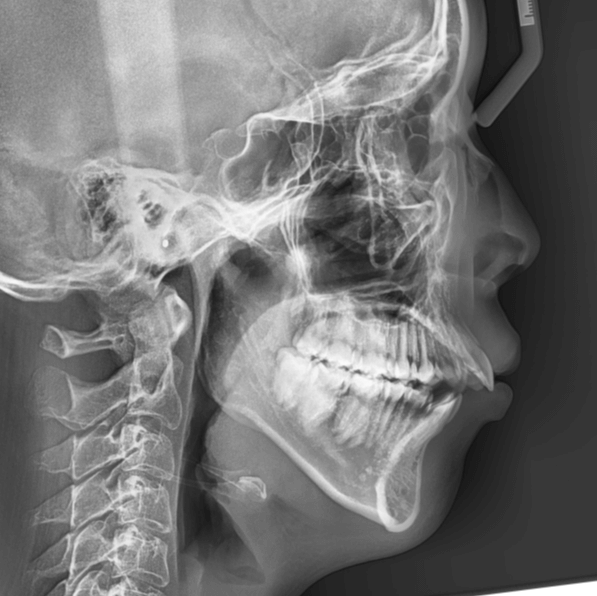

咬み合わせが逆であること(反対咬合)が気になる

| 年齢・性別 | 15歳 女性 |

|---|---|

| 主訴 | 咬み合わせが逆であること(反対咬合)を気にされて来院された女性。見た目や機能面の改善を希望されていました。 |

| 治療期間・回数 | 4年4ヶ月・28回 |

| 費用 | 900,000円 |